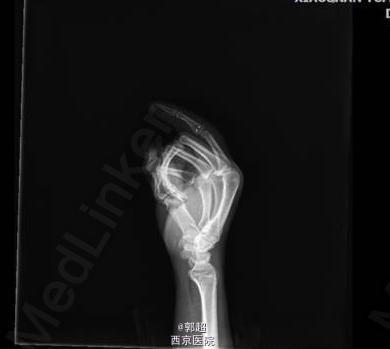

示指近侧指间关节离断再植

患者男,42岁,外伤致右手示指近侧指间关节离断1天。治疗计划“锚钉修复掌板、侧副韧带,恢复关节的稳定性。